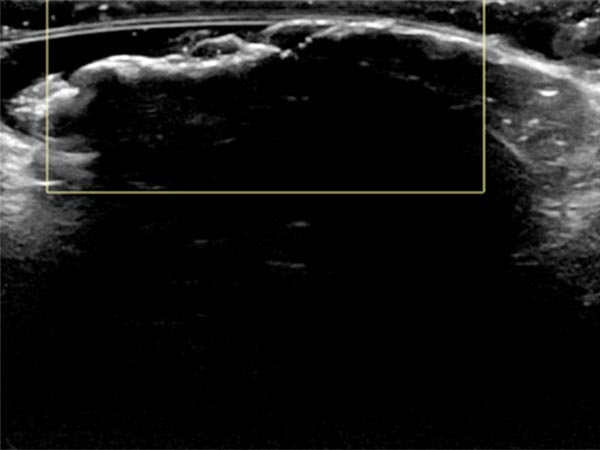

In der Sonographie (B-Bild) findet sich durch den hohen Bindegewebsanteil an der Oberfläche des Nävus direkt eine totale Schallreflexion mit einem ausgeprägten Schallschatten. Die Läsion selbst ist nicht darstellbar.

In der farbkodierten Duplexsonographie (FKDS) zeigt sich ebenfalls die totale Schallreflexion. Auch bei sehr empfindlicher Einstellung für Blutfluss (6 cm/s) keinerlei Perfusion feststellbar.